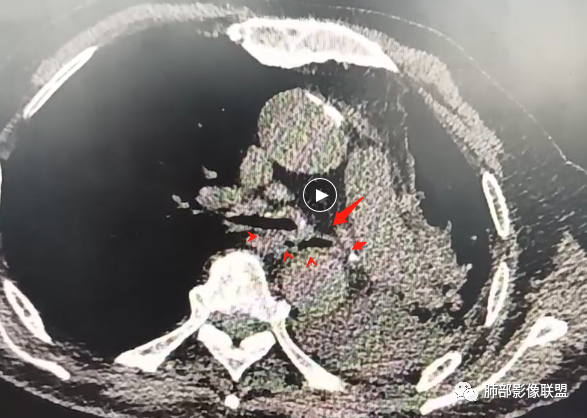

男,81,咳嗽、胸闷20天,咯血2天。胸部CT:左主支气管狭窄、管壁环形增厚,部分层面左主支气管壁高密度,骨化?左叶裂广泛不均匀增厚,结节感。3个月后左侧胸廓塌陷,左主支气管狭窄明显,左肺大部不张。考虑支气管TB并肺不张?支气管骨化?鉴别Ca、淀粉样变、复发性多软骨炎、GPA等

3/18:左主支气管壁弥漫增厚

补充视频:2021年3月17日

复查时间:2021年8月11日

病人当时住院抗感染治疗后症状有改善,没有进行其他化验检查,嘱咐3月后复查。病人直到喘的厉害才复查。